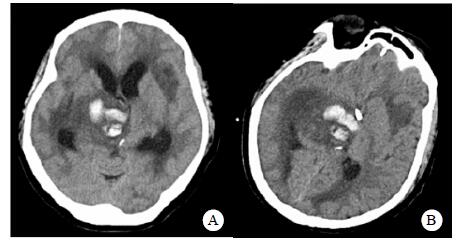

患者,女,54岁,工人,因“头晕5 d”于2019年9月29日至浙江大学附属第二医院急诊就诊。5 d前患者无明显诱因出现头晕,伴行走不稳、四肢乏力,无发热、咳嗽咳痰、胸闷气促、恶心呕吐、四肢抽搐等,未就诊。我院急诊头颅磁共振(MRI)示:右侧丘脑及左侧岛叶异常信号,局部累及右侧中脑(图 1),考虑脑多发占位性疾病。在急诊抢救室予甘露醇100 mL静滴脱水降颅压等对症治疗,5 h后患者逐渐意识模糊。急查血常规:白细胞16.1×109/L,中性粒细胞百分比73.4%;头颅CT示右侧丘脑、左侧岛叶病变,伴脑室扩张(图 2);急诊行“双侧脑室外引流术”,术中引流液呈淡血性。术后诊断:⑴(右侧丘脑)颅内占位性病变,脓肿首先考虑,肿瘤需排除;⑵脑积水;⑶脑疝。患者带气管插管转入ICU进一步治疗。当时体温38.3℃,脉搏99次/min,呼吸频率24次/min,血压169/87 mmHg(1 mmHg= 0.133 kPa),颈软,神志昏迷,右侧瞳孔3 mm,左侧瞳孔2.5 mm,对光反射迟钝。双肺呼吸音粗,可闻及少量啰音。左侧病理征阳性。患者3个月前曾因“反复胸闷气促伴发热1个月余”在本院风湿科住院,当时胸部高分辨CT示两肺间质性肺炎、下叶为著(图 3);血化验示血沉偏高,抗心磷脂抗体阳性;诊断为“间质性肺炎”,住院期间予甲泼尼龙40 mg/d静滴×8 d,60 mg/d静滴×6 d,共住院14 d;出院后予口服甲泼尼龙40 mg/d联合雷公藤多苷片每次20 mg,一日2次治疗;此后规范于本院门诊复诊。本次起病前2个月甲泼尼龙已减量至36 mg/d口服治疗。

| A:右侧丘脑、左侧岛叶病变,伴脑室扩张;B:双侧脑室钻孔引流术后改变,脑室扩张较前(2019-09-29)好转,右侧丘脑、左侧岛叶病变伴出血 图 2 患者2019-09-29头颅CT平扫(A)和2019-09-30头颅CT平扫(B) |

转入ICU后呼吸机辅助通气、甘露醇100 mL/8 h静滴脱水、头孢呋辛1.5 g/12 h静滴抗感染,肠内营养等支持治疗。当晚血常规:白细胞13.3×109/L,中性粒细胞百分比85.3%,C反应蛋白17.1 mg/L,降钙素原0.64 ng/mL。脑室外引流术后次日血化验:白细胞16.6×109/L,中性粒细胞百分比92.8%,C反应蛋白78.4 mg/L;从脑室外引流管留取脑脊液检验:有核细胞6×106/L,红细胞1 960×106/L,蛋白含量1.717 g/L,葡萄糖4.72 mmol/L,细菌培养阴性,涂片未找到细菌;复查头颅CT示:脑室扩张好转,右侧丘脑、左侧岛叶病变伴出血(图 2);胸部CT示,两肺间质性肺炎下叶为著,较前(2019年6月21日)部分好转(图 3)。考虑到炎症指标升高,遂改哌拉西林他唑巴坦3.375 g/12 h静滴抗感染。此后经脑室外引流管反复留取脑脊液送检涂片及培养均阴性。术后第5天行“导航下立体定向颅内病灶活检术+双侧omaya囊置入术”,术中穿刺液呈黄色黏稠脓性,考虑脑脓肿,留取脓液送高通量测序(next-generation sequencing, NGS),并升级为美罗培南2 g/8 h联合利奈唑胺0.6 g/12 h静滴抗感染治疗。术后第7天患者突发血压升高、瞳孔不等大,昏迷程度加深;急查头颅CT示,双侧脑室钻孔引流术后改变,双侧侧脑室引流管走形区出血伴血肿形成;右侧丘脑区积液、积血,双侧脑室积血新发(图 4),甘露醇加量至250 mL/8 h联合地塞米松5 mg/6 h静滴加强脱水;当日术中脓液高通量测序结果回报:皮疽诺卡菌(序列数52 867个)、支气管戈登菌(序列数10个)。确诊脑诺卡菌病,抗菌治疗方案改为亚胺培南西司他丁0.5 g/6 h静滴,联合利奈唑胺0.6 g/12 h和复方磺胺甲恶唑片(0.48 g/片)3片/6 h口服。此后患者仍伴低热,炎症指标呈上升趋势。术后2周患者再次突发血压升高、瞳孔不等大、对光反射消失、神志深昏迷,急查头颅CT示再发脑疝(图 5),急诊行“去骨瓣减压术+脑内血肿清除术”,术后患者仍呈深昏迷状态,双侧瞳孔散大、对光反射消失,次日自动出院。